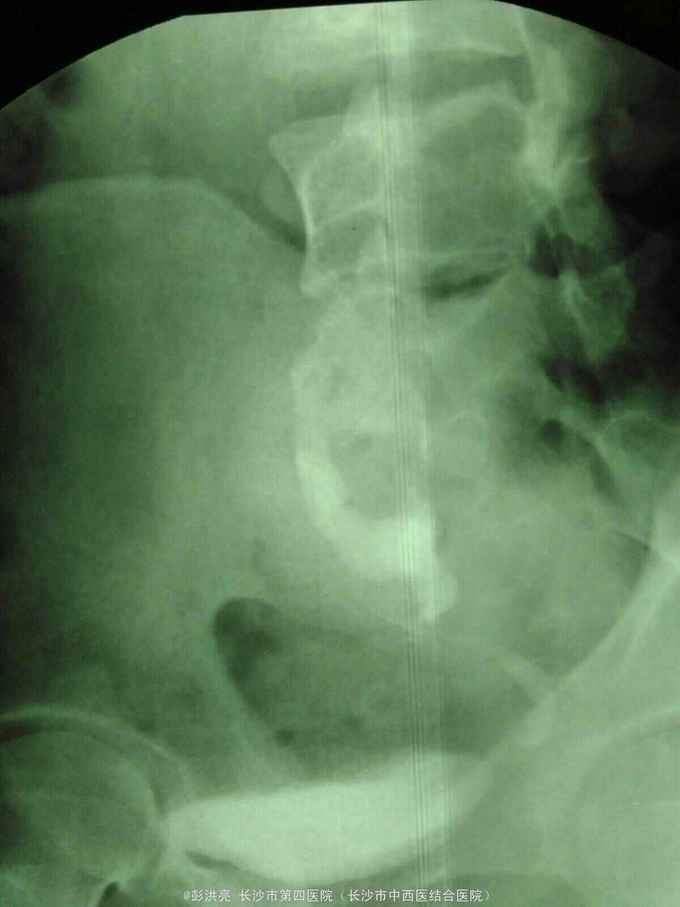

男性,25岁,左腰痛入院。2年前在外院发现左侧盆腔异位肾并肾盂输尿管移行处结石行腹腔镜下切开取石术。现CT示左侧盆腔异位肾并多发结石。术前其他检查正常。

请问该患者如何处理。